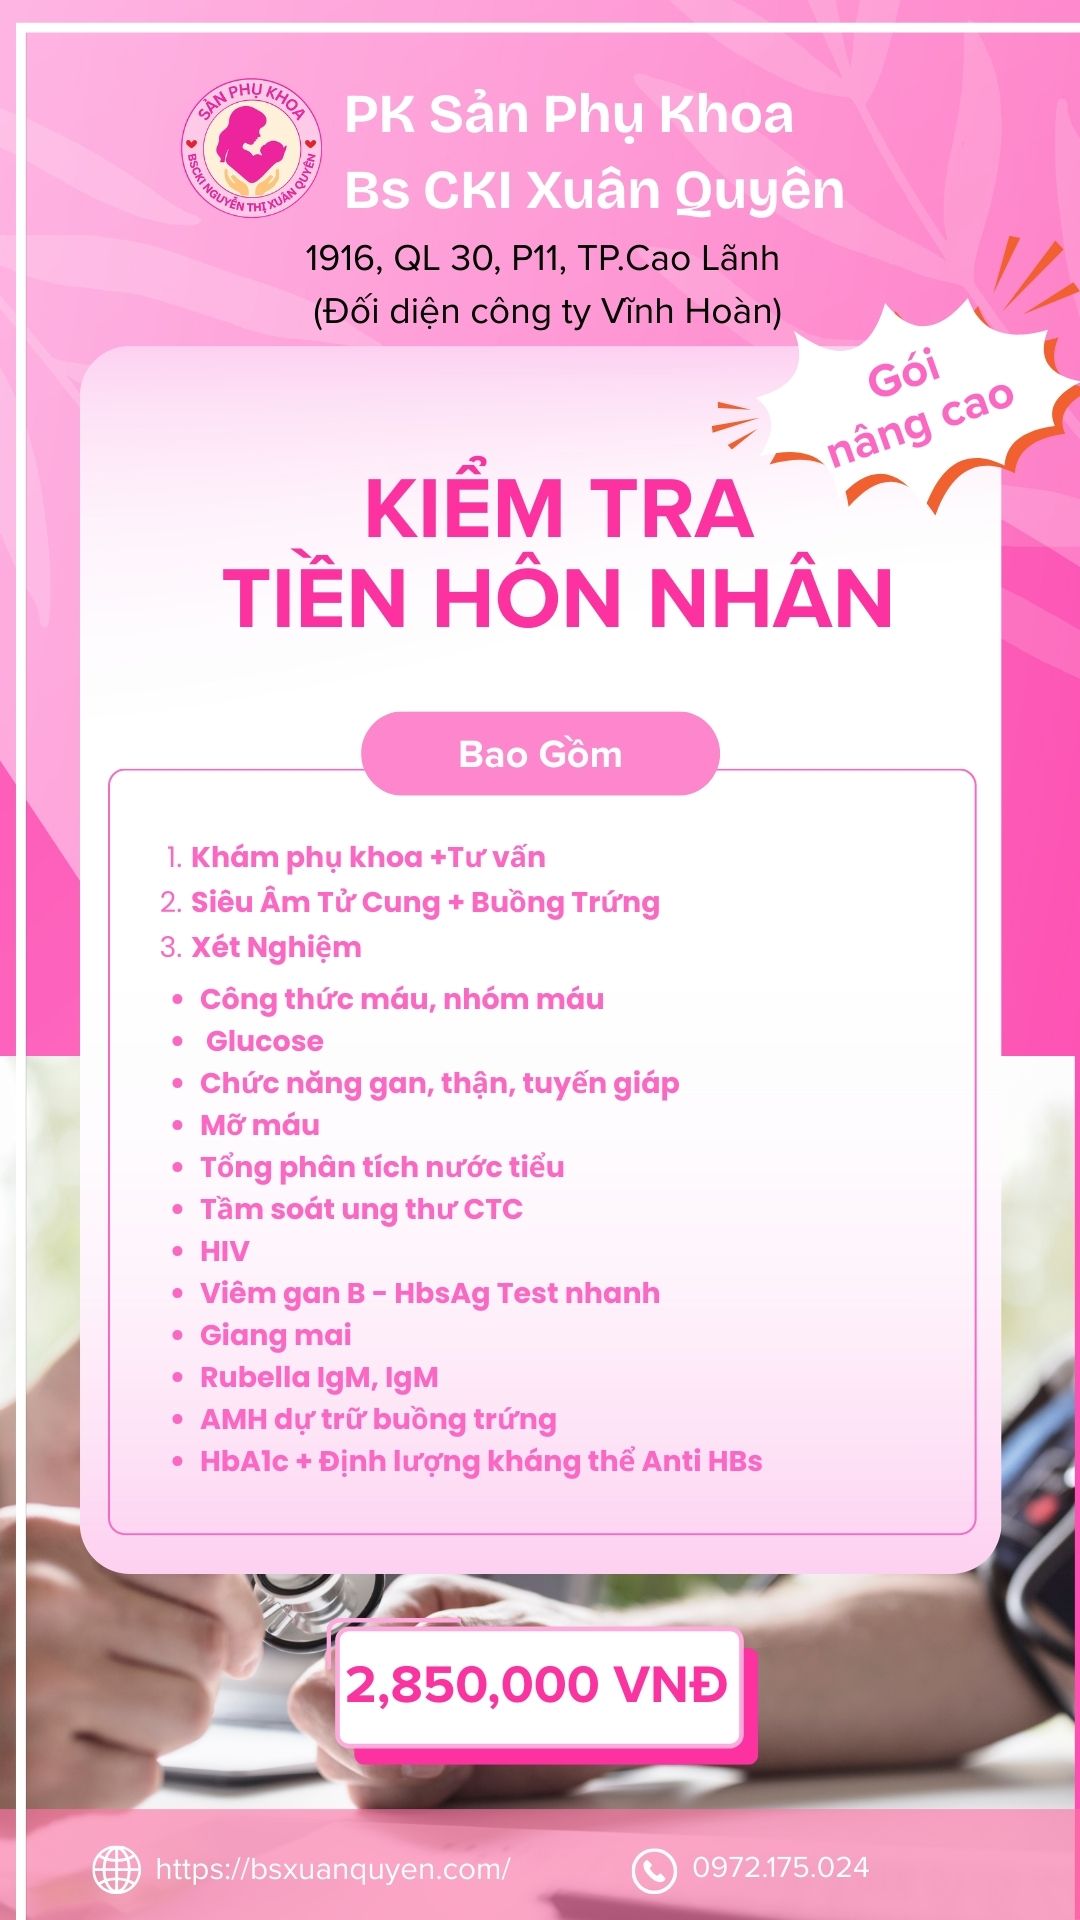

Gói kiểm tra tiền hôn nhân nâng cao

Xét nghiệm máu mẹ Nâng cao

Công thức máu, nhóm máu Chức năng gan, thận, tuyến giáp Bệnh lây truyền mẹ con: HIV, Viêm Gan, Giang mai Rubella

Siêu âm phụ khoa qua ngã Âm đạo

Siêu âm kiểm tra tử cung + buồng trứng Mục đích: kiểm tra phát hiện bất thường như nhân xơ tử cung, u nang buồng trứng, đánh giá nội mạc tử cung, phát hiện thai sớm,….